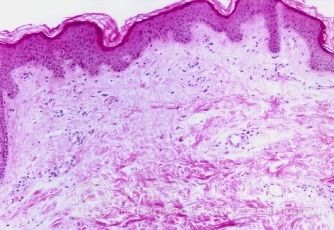

1、排毒一定要*:荨麻疹患者会因为血热、血瘀、血燥等"血毒"引起痒痛,使表皮*分化失控,速度是正常皮肤分化的数倍。表皮*分化失控将分化不全的皮肤功能出现障碍,导致血毒渗出血管,在皮肤上形成血点,并且有痒痛感。